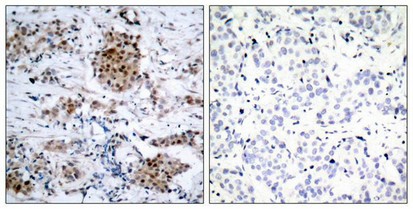

Immunohistochemical analysis of paraffin-embedded human breast carcinoma tissue using Estrogen Receptor-a(Phospho-Ser167) Antibody(left) or the same antibody preincubated with blocking peptide(right).